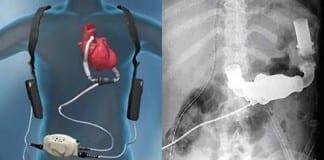

Study Rundown: Patients with high-mortality medical conditions are often presented with different choices for therapy. Decision making reflects patient values, understanding of the underlying condition, and perceived risks and benefits of the available interventions. In patients with severe heart failure who are not transplant candidates, destination therapy with LVAD may prolong life, but also involves alterations in caregiver needs, lifestyle, and intervention-related complications. Patient education on LVAD destination therapy is limited by poor communication by the clinician, and biased industry provided literature on available devices. The current study sought to evaluate the impact of an education and literature-based decision aid program on patient comprehension and concordance with pre-existing values. The study found that the intervention improved patient knowledge, and concordance between values and patient choice of therapy. However, concordance of patient values and final therapy received at 6 months did not significantly change following the therapy.

In-Depth [randomized controlled trial]: This study, the Multicenter Trial of a Shared Decision Support Intervention for Patients and their Caregivers Offered Destination Therapy for End-Stage Heart Failure (DECIDE-LVAD), was a hospital-level randomized, stepped-wedge (phased roll-out) trial involved 6 MCS programs in the United States. During the 20-month enrollment period, clinician-patient dyads were included if they were 18-years or older with severe heart failure not a candidate for transplant and being considered for destination LVAD therapy. The intervention consisted of a 2.5-hour clinician training session on shared decision support, and the use of video and pamphlet decision aids for patients. The primary outcome of decision quality was assessed by evaluation of patient knowledge through a 10-item test, and concordance between patient value score and treatment choice.